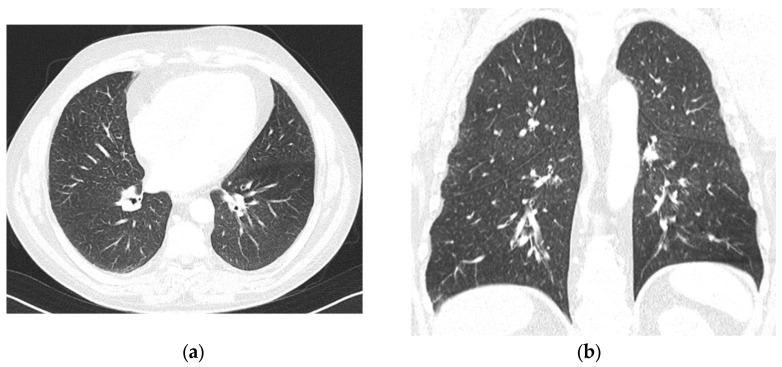

Background and Clinical Significance: Intermediate- to high-risk Myelodysplastic Syndrome (MDS), according to the Revised International Prognostic Scoring System (IPSS-M), confers a high risk of progression into acute myeloid leukemia. Treatment with hypomethylating agents, including azacitidine and decitabine, represents the current standard of care. In eligible patients, hypomethylating agents are used as a bridge for allogeneic stem cell transplantation, currently the only curative approach in these malignancies. The most common side effects of hypomethylating agents are myelosuppression, cutaneous injection site reactions (when azacitidine is given subcutaneously), and gastrointestinal symptoms. Uncommon, disabling, and long-lasting side effects represent a threat to effective treatment in this group of patients. Case Presentation: We describe the case of a 49-year-old male patient with IPSS-M intermediate-risk MDS, intended to receive first-line treatment with azacitidine followed by allogeneic stem cell transplantation. The first, late-onset azacitidine reaction was observed 48 h after the first exposure, with cutaneous and respiratory toxicity, followed by the late-onset recurrence of symptoms after azacitidine withdrawal and decitabine introduction. Conclusions: This case highlights atypical, disabling, and long-lasting drug reactions to two hypomethylating agents, with the persistence of hypersensitivity manifestations months after medication withdrawal.